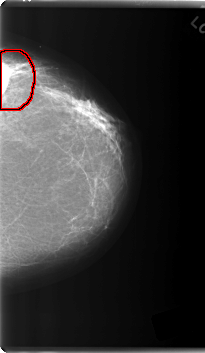

FILE: C_0219_1.LEFT_CC.OVERLAY

TOTAL_ABNORMALITIES 1

ABNORMALITY 1

LESION_TYPE MASS SHAPE OVAL MARGINS CIRCUMSCRIBED

ASSESSMENT 5

SUBTLETY 5

PATHOLOGY MALIGNANT

TOTAL_OUTLINES 1

BOUNDARY

LEFT_CC LINES 6000 PIXELS_PER_LINE 3480 BITS_PER_PIXEL 12 RESOLUTION 50 OVERLAY